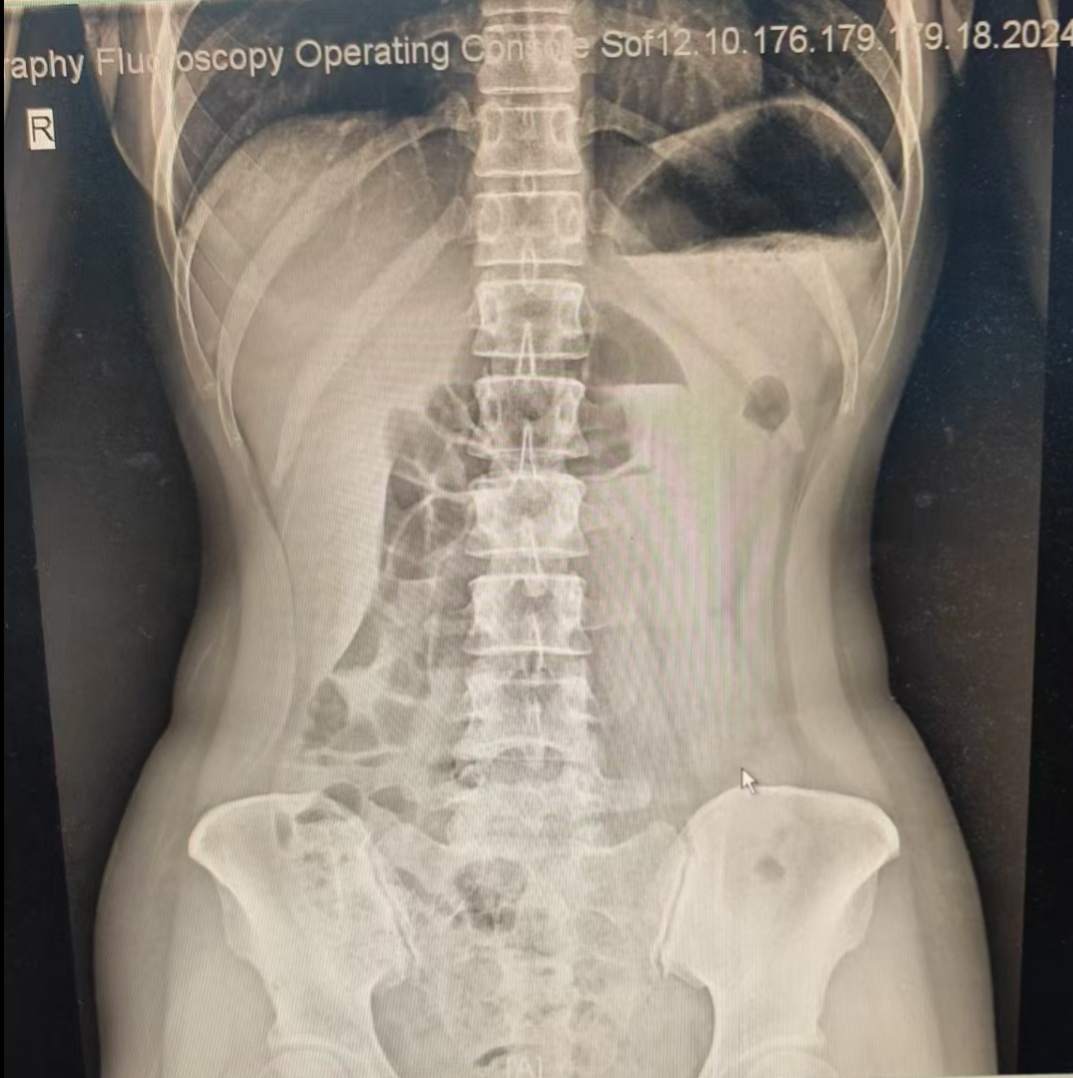

胸腹部X线报告:肠梗阻

CT报告:未达到肠梗阻的指标,算是胃肠道积气。